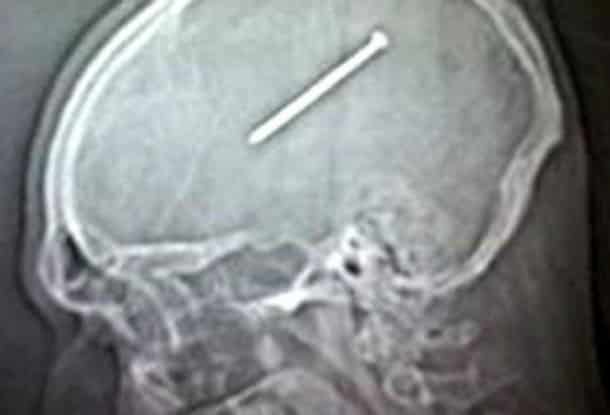

33 radiographies qui prouvent que les gens font des choses douteuses avec leur corps !